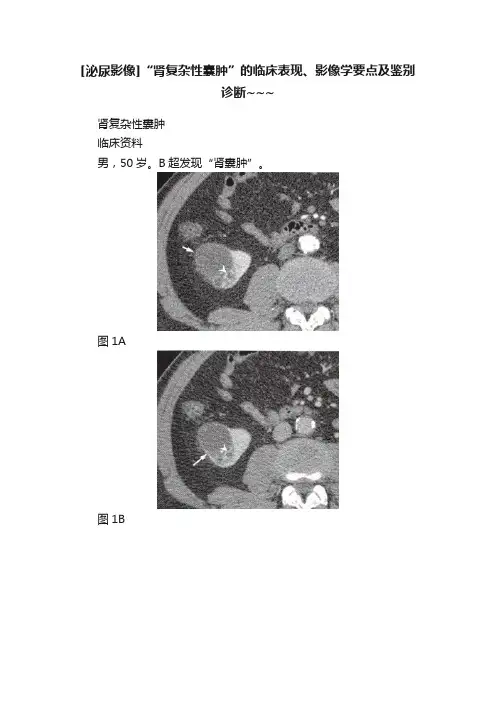

[泌尿影像]“肾复杂性囊肿”的临床表现、影像学要点及鉴别诊断~~~肾复杂性囊肿临床资料男,50岁。

B超发现“肾囊肿”。

图1A图1B图1C图1D图1E图1F影像学报告描述轴位肾增强CT皮质期(图1A),右肾下极见一45mm×49mm×59mm大小囊样病灶(箭),向外下肾周间隙突出。

病灶内囊液密度稍高,CT值为10〜18HU,病灶外侧部分形态规则光滑,而内部分形态不规则,壁增厚,可见增厚的分隔及结节(箭头),有强化,增强后CT值为104〜132HU。

增强髓质期(图1B),更清楚地显示增厚囊壁(箭)及囊内间隔和结节(箭头)。